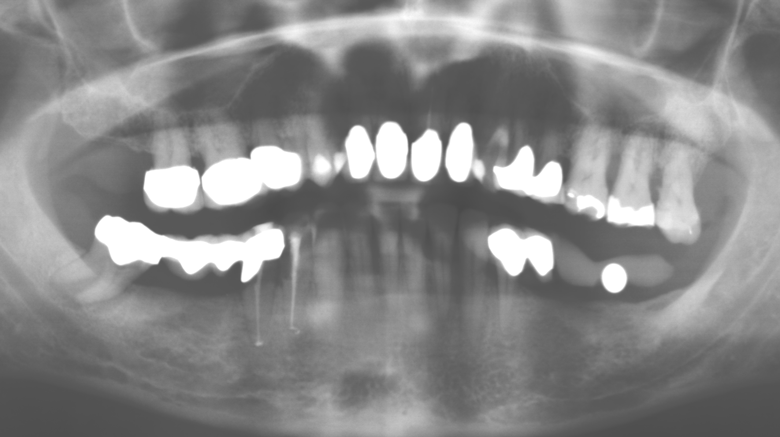

A causa della presenza di problematica parodontale, SPT è stata eseguita ogni tre mesi nei primi anni successivi all'inserimento. Il paziente ha dimostrato un alto grado di motivazione e una buona costanza. Le profondità di tasca registrate ogni anno hanno rivelato una situazione parodontale stabile con un indice BOP inferiore al cinque per cento. Sulla base della situazione parodontale stabile e della buona collaborazione da parte del paziente, l'intervallo di richiamo è stato esteso ogni sei mesi a partire dal sesto anno dalla fase della funzione protesica. A seguito della modifica dell'intervallo di richiamo, la rispettiva documentazione annuale dello stato parodontale ha continuato a rivelare una situazione parodontale stabile senza aumento della profondità della tasca e un indice BOP inferiore al cinque per cento (Fig. 2a eb).

Fig. 2: Le profondità delle tasche registrate ogni anno con SPT semestrale non mostrano una tendenza in aumento e un indice BOP inferiore al 5% con una situazione parodontale in gran parte priva di infiammazione. a) status PERIO nel 2011 (dopo cinque anni con impianti). b) status PERIO nel 2016 (dopo dieci anni con impianti).